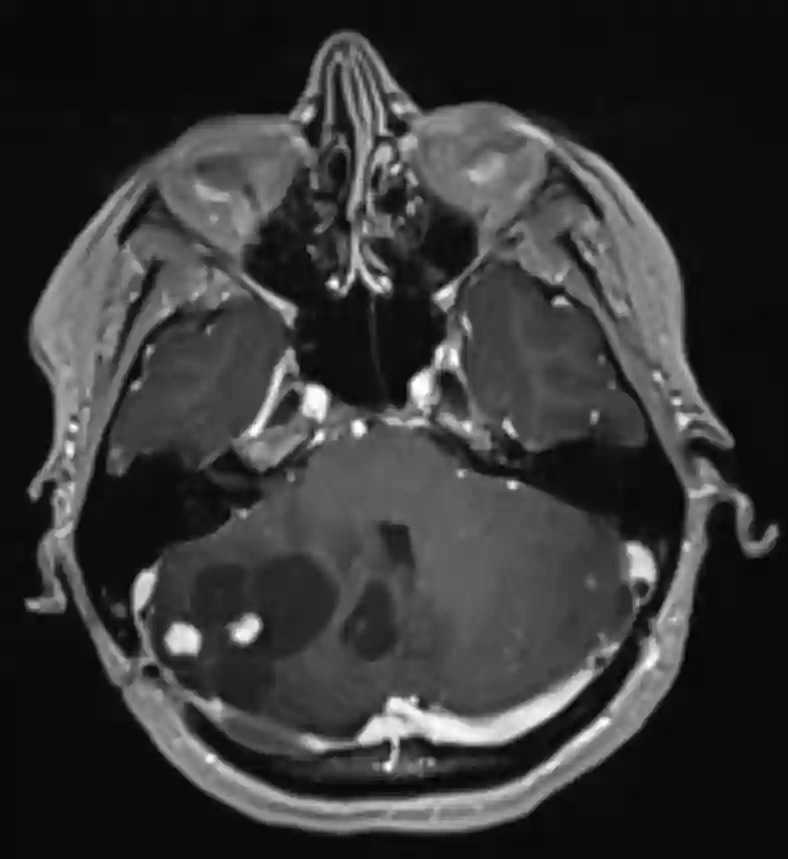

Bildgebung

Der Goldstandard in der Bildgebung von Hämangioblastomen ist die MRT Bildgebung. In einer digitalen Subtraktionsangiographie zeigt sich häufig ein stark vaskularisierter Nodulus mit Feedergefäßen, welcher suggestiv für ein Hämangioblastom ist.